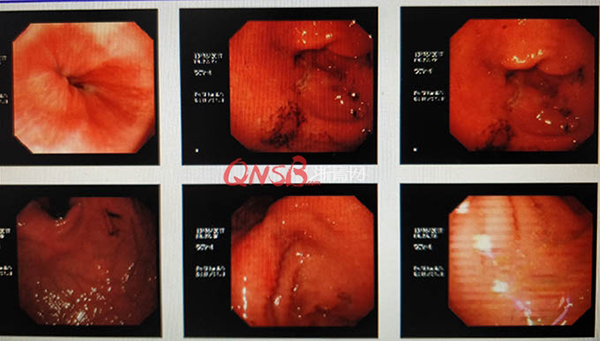

檢查結(jié)果出來后,小周大吃一驚,本以為自己的胃很健康,卻不想胃粘膜廣泛充血糜爛,長了兩個(gè)巨大的潰瘍(直徑大于2厘米),還有出血和咖啡色血痂。

網(wǎng)絡(luò)圖